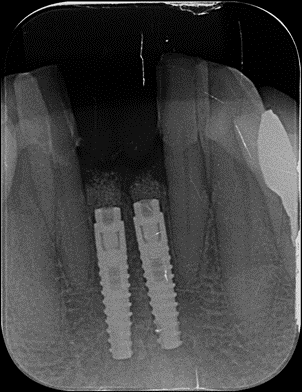

Em um primeiro momento foi feito um pequeno desgaste com ponta diamantada nas faces mesiais dos dentes 32 e 42 para aumentar o espaço mésio-distal. Com a paciente sob anestesia local adequada, procedeu-se às exodontias dos incisivos 31 e 41 utilizando técnica minimamente traumática. Realizou-se incisão intrasulcular ao redor dos dentes e uso delicado de periótomo e alavancas de pequeno porte, promovendo a luxação e remoção cuidadosa das raízes sem descolar retalhos mucoperiostais. Essa técnica conservadora preservou os tecidos peri-implantares – em especial a papila interdental entre os dentes 32 e 42 – e manteve a integridade das paredes ósseas alveolares, fundamentais para a estética e cicatrização. Confirmada a ausência de fenestrações ou deiscências ósseas pós-exodontia, prosseguiu-se imediatamente com a osteotomia para instalação dos implantes. Seguiu-se o protocolo de fresagem recomendado pelo fabricante para o implante Stretto, utilizando sequência de brocas de diâmetro incremental adequado à densidade óssea presente. O conjunto Stretto apresenta brocas desenhadas para preparos precisos e minimamente invasivos, facilitando a instalação em sítios com espaço limitado. A preparação atingiu estabilidade primária suficiente apicalmente, permitindo o travamento dos implantes nos alvéolos frescos. Foram instalados dois implantes cone morse Stretto (Ø 3,0 mm x 11,5 mm) nas posições 31 e 41, posicionados de forma centralizada nos respectivos alvéolos e com paralelismo adequado entre si. Importante notar que o implante Stretto foi desenvolvido especificamente para situações críticas de espaço protético e ósseo reduzido, combinando facilidade cirúrgica e versatilidade protética para reabilitar tais casos.

Importante notar que o implante Stretto foi desenvolvido especificamente para situações críticas de espaço protético e ósseo reduzido, combinando facilidade cirúrgica e versatilidade protética para reabilitar tais casos. Ao término da inserção, os implantes apresentavam boa estabilidade primária (torque moderado), e optou-se por não os submeter à carga imediata direta, priorizando a preservação do enxerto e a osseointegração sem micro movimentação excessiva. Então, foi instalado um cicatrizador com altura transmucosa baixa.

Extra Graft XG-13 na preservação alveolar

Neste caso, a preservação do volume alveolar pós-extração — especialmente da delicada tábua óssea vestibular dos incisivos inferiores — foi fundamental para garantir a previsibilidade estética e funcional do tratamento. Após a instalação dos implantes, os GAPs peri-implantares foram preenchidos com o Extra Graft XG-13 (Implacil Osstem), um biomaterial xenógeno composto por 75% de hidroxiapatita bovina e 25% de colágeno tipo I. Sua aplicação visa controlar a remodelação óssea natural e sustentar os tecidos moles, mantendo o contorno gengival e a estabilidade óssea ao longo do tempo.